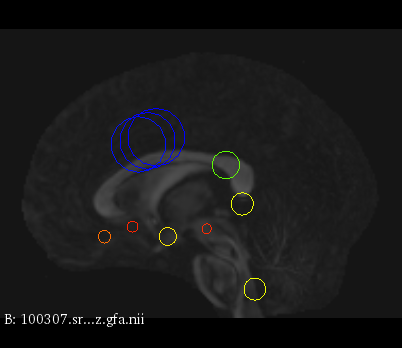

Figure 3 provides a scale-space visualization of feature matches for a single pair of MZ twins and NT siblings, where scale information is represented using the circle radius. Note that circles represent the intersection of 3D spheres with the visible slice and, thus, non-intersecting features are hidden in this 2D visualization.

It can be seen that different image modalities generally result in distinct, complementary feature correspondences throughout the brain, allowing a rich characterization of both anatomical and connectivity structure. In T1 and T2 images, features are mainly located in the frontal lobe, corpus callosum and brain stem. Smaller-scale features are also visible along various cortical regions, as well as in sub-cortical structures near the basal ganglia. Although highly correlated, T1 images show significantly more feature matches than T2 images. Moreover, images based on diffusion measures have less matches than in structural modalities. These matches are located mostly inside or near to white matter: larger-scale features in the corpus-callosum, and smaller-scale ones in the brain stem and along white matter bundles. While not shown in the figure, the set of matches found by combining two modalities (e.g., T1 + T2) generally corresponds to the union of those obtained with these individual modalities.

Comparing different sibling types, we observe a greater number of matches between MZ twins than NT siblings. This observation, which is easier to visualize in T2 and GFA images, is consistent with other analyses on twin datasets. In terms of feature location and scale, no obvious pattern can be seen when comparing these two sibling types. However, a more detailed analysis would be required to validate this assertion.